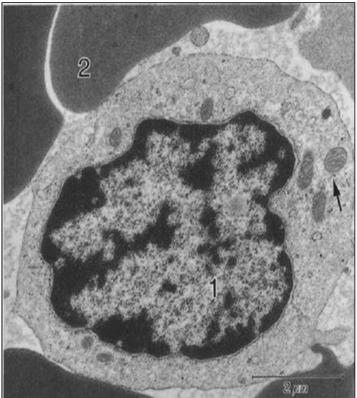

monocito

Qué es el Sistema Monocito–Macrofágico